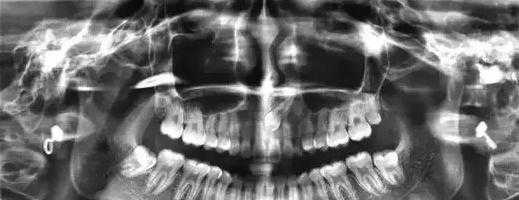

2,拍片子:

进行必要的牙体牙髓牙周检查,确保在矫治过程中牙体形态、牙周状况稳定。拍摄X光牙齿及头部颌骨照片。目的是确定颌面及牙列畸形的分类类型,骨骼发展方向等。便于以后制定准确的矫治方法。